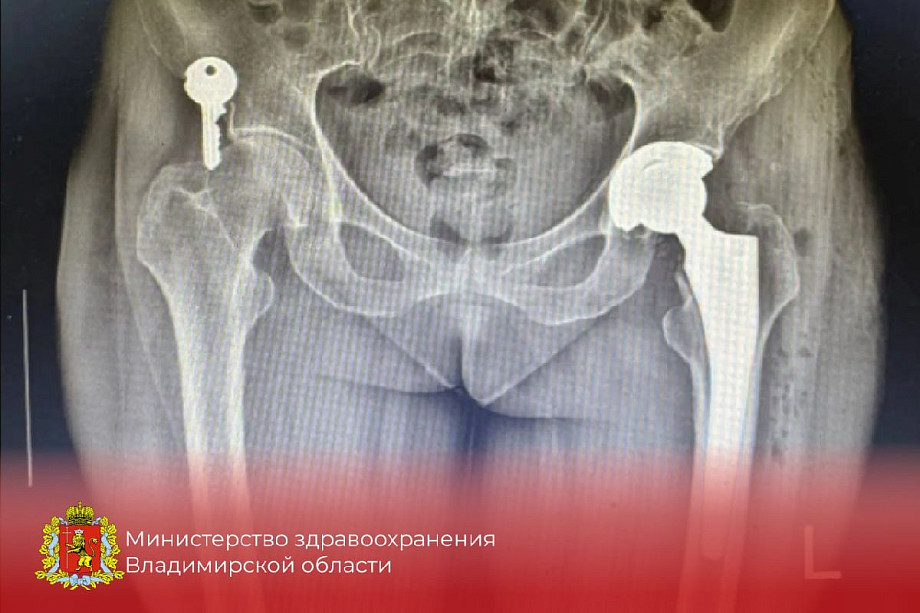

В ковровской центральной больнице хирурги в сотрудничестве с ведущим областным специалистом В.С. Красильниковым успешно провели первые операции по эндопротезированию тазобедренного сустава при сложных переломах. Ключевой особенностью стала работа с самыми тяжёлыми случаями — переломами шейки бедренной кости, которые раньше часто были приговором для пожилых пациентов. Теперь врачи могут полностью заменить разрушенный сустав, что кардинально меняет прогнозы на восстановление. Две уже выполненные операции открыли для жителей Коврова и района доступ к передовой медицинской помощи, ранее доступной лишь в крупных федеральных центрах. Это знаменует новый этап в развитии высокотехнологичного здравоохранения на местном уровне. ГТРК "Владимир"

Фото: Минздрав Владимирской области